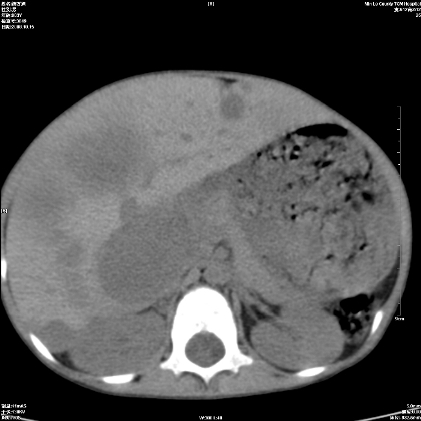

标题: PED1609:男性,3岁。彩超示肝Ca. [打印本页]

标题: PED1609:男性,3岁。彩超示肝Ca.

3岁;肝低密度灶;有钙化;有转移灶;考虑肝母细胞瘤;查afp

支持肝母细胞瘤肝内转移

考虑神经母细胞瘤并肝转移

考虑:1、右侧后下纵隔畸胎瘤。

2、肝脏多发血管内皮细胞瘤。

建议:增强确诊。